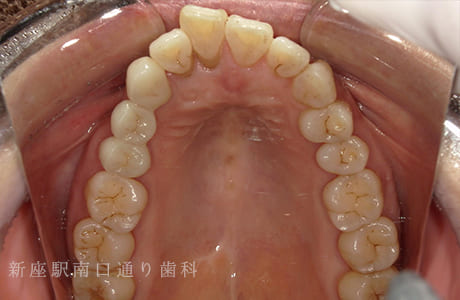

CASE.04

右上にフルジルコニアブリッジで

修復した症例

術前

術中

術後年

- 主訴

- 歯がないところを治したい

- 治療法

- 右上にフルジルコニアブリッジで修復

- 治療期間

- 1ヶ月半

- 費用

- ¥280,000(税込)

【リスク・副作用】

過度の咬合や衝撃で割れることがあります。治療直後は歯や歯茎に一時的な違和感や痛みが出ることがあります。